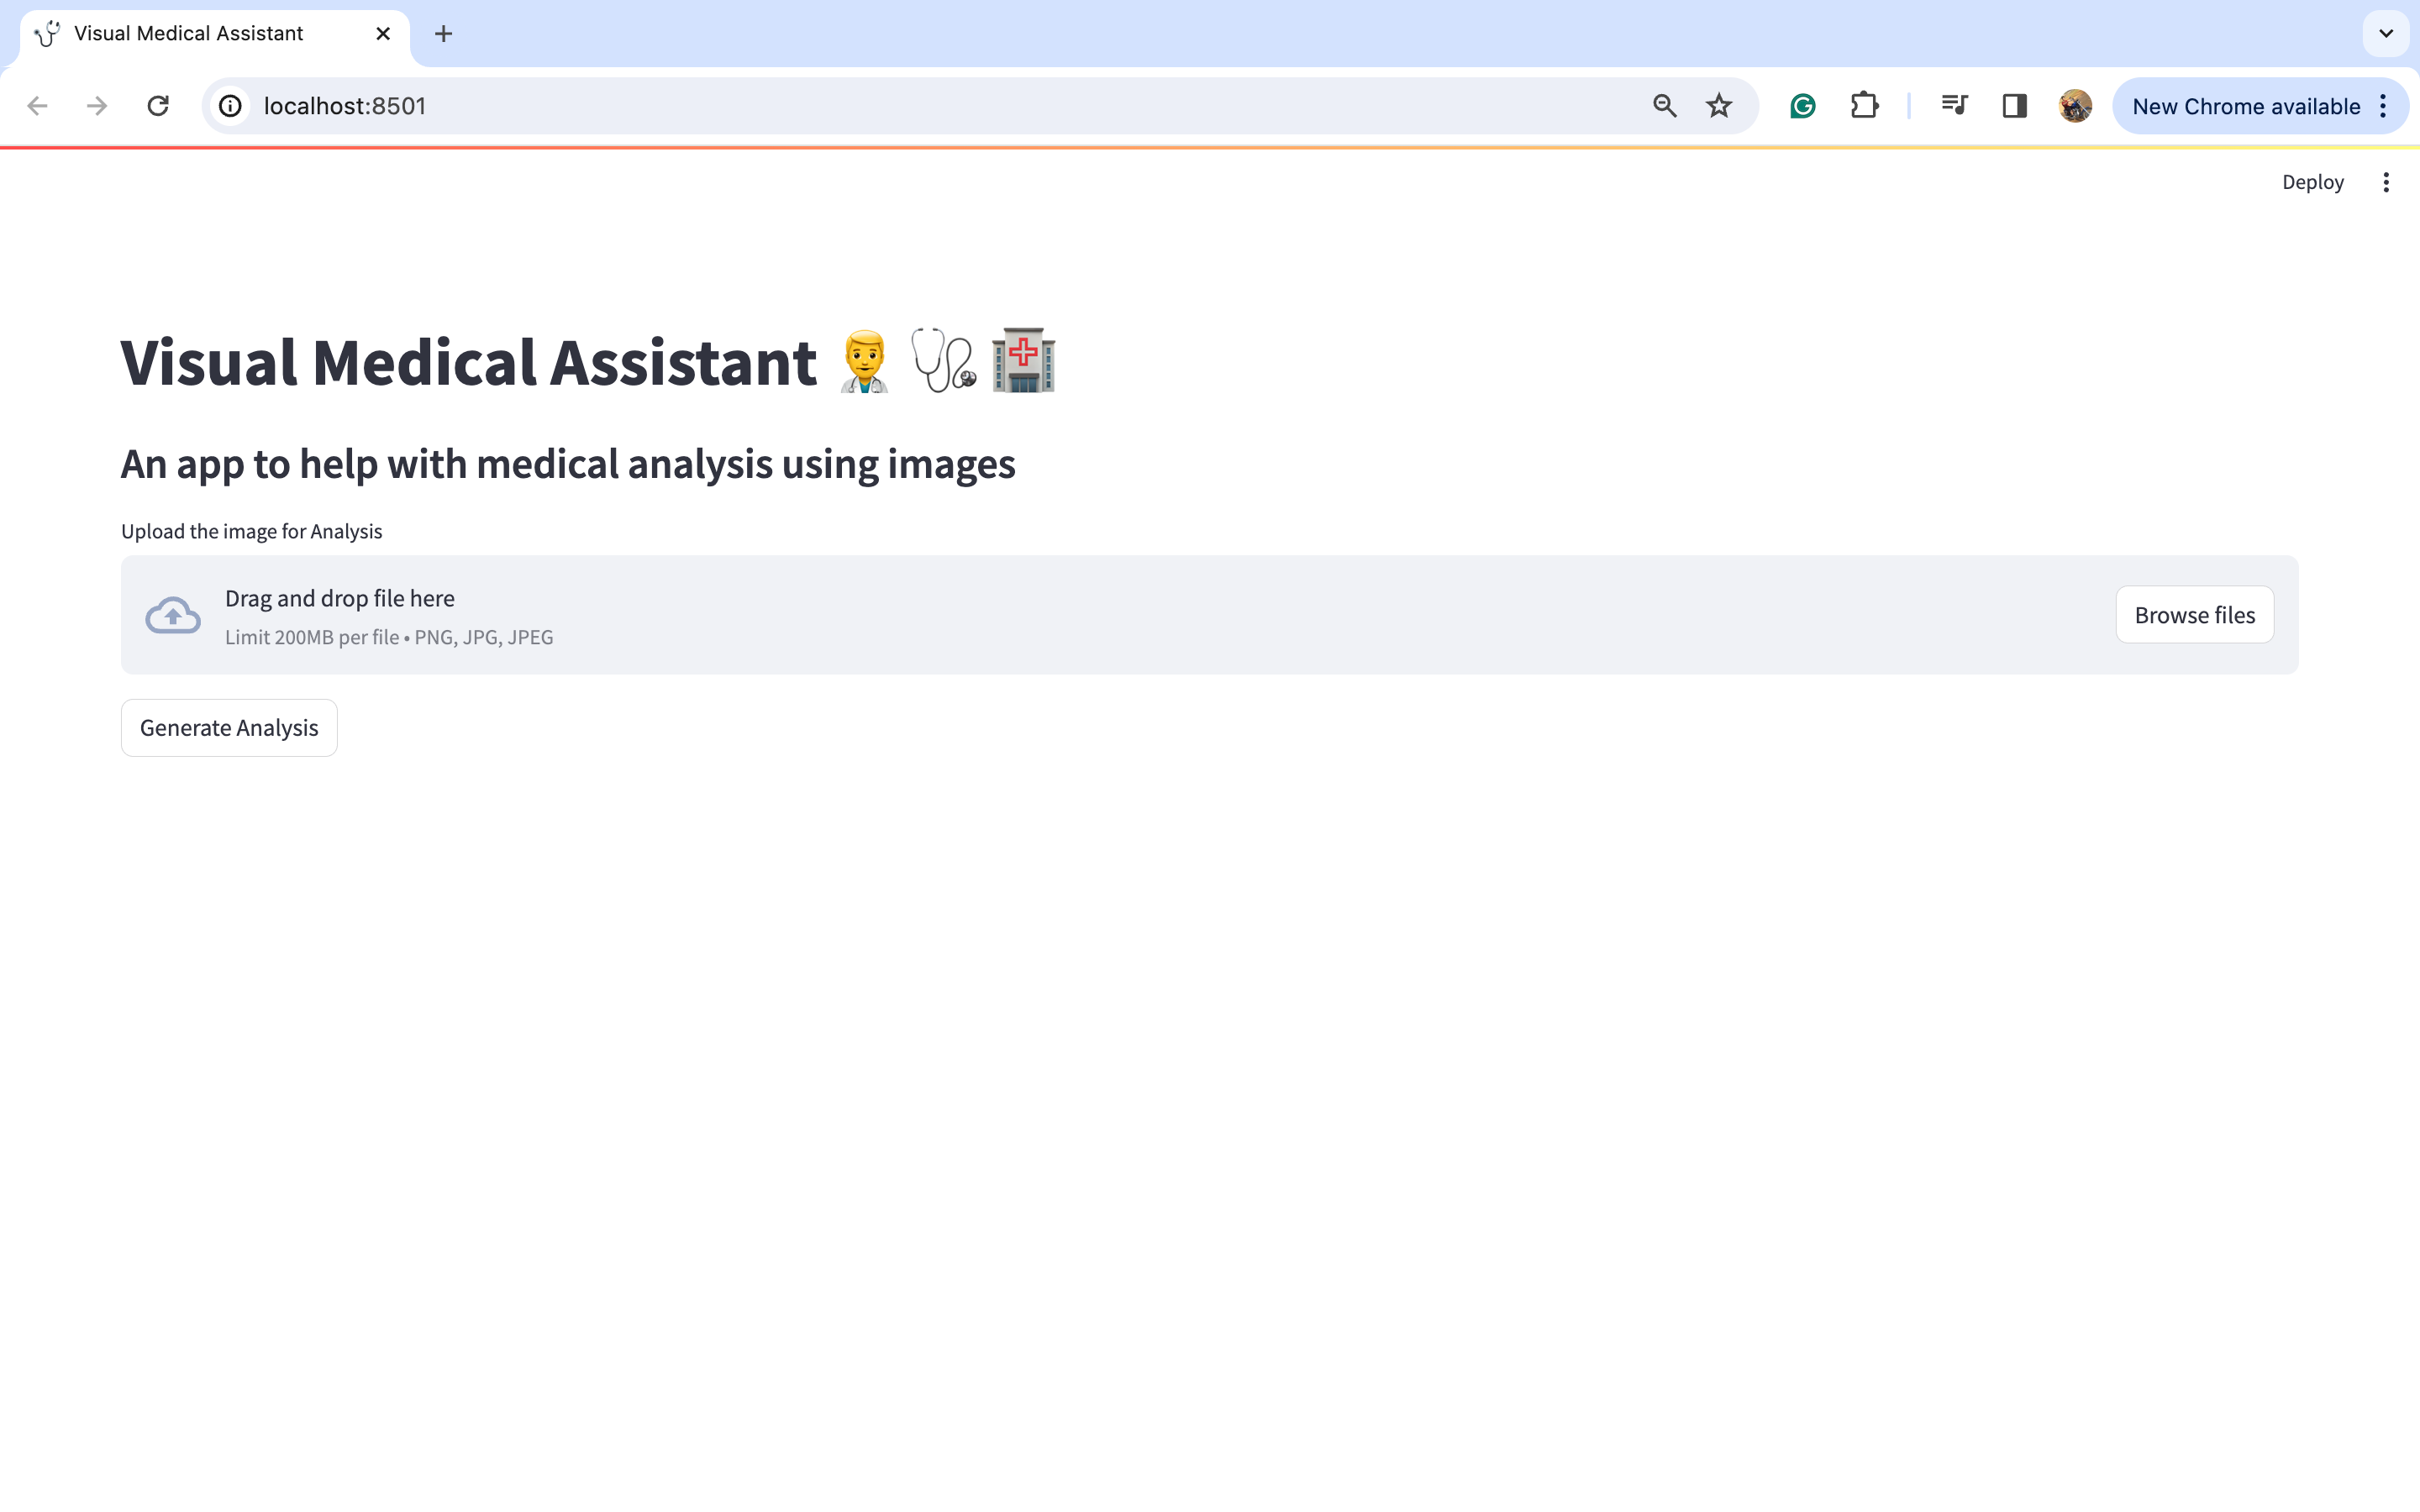

看它如何运行

我们需要打开Python终端并执行以下命令来调用streamlit应用程序。确保将目录更改为与app.py相同的目录。

streamlit run app.py

输出:

现在,我们将上传一些图片并尝试查看输出。让我们尝试查看一张歪曲图片的分析结果。我从谷歌下载了同样的图片。

让我们点击“浏览文件”按钮上传这张图片。